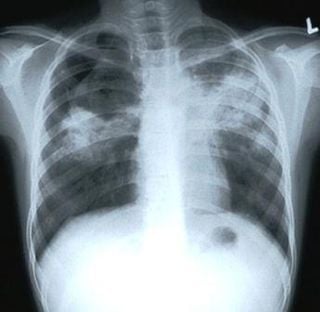

Tuberculosis as seen on X-ray

Wikipedia defines TB as a common and in many cases lethal, infectious disease caused by various strains of mycobacteria, usually Mycobacterium tuberculosis. Tuberculosis usually attacks the lungs but can also affect other parts of the body. It is spread through the air when people who have an active MTB infection cough, sneeze, or otherwise transmit their saliva through the air. The classic symptoms are a chronic cough with blood-tinged sputum, fever, night sweats, and weight loss (the last giving rise to the formerly prevalent colloquial term “consumption”). Infection of other organs causes a wide range of symptoms. Diagnosis relies on radiology (commonly chest X-rays), a tuberculin skin test, blood tests, as well as microscopic examination and microbiological culture of bodily fluids. Treatment is difficult and requires long courses of multiple antibiotics.